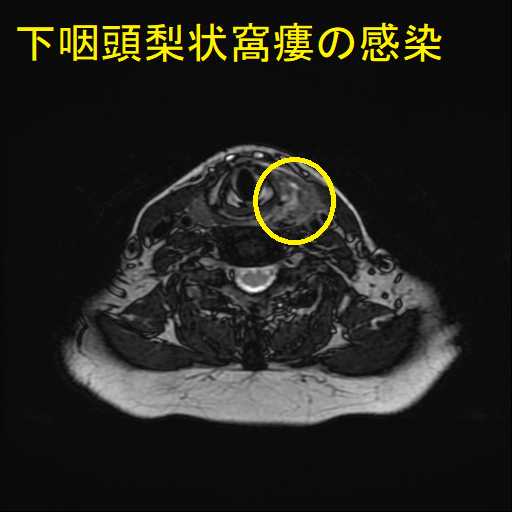

- 通常の造影頸部CTで、甲状腺外の膿瘍形成と、その範囲が明らかになります。

- 下咽頭部造影CTで、下咽頭梨状窩瘻を見つけます。

急性化膿性甲状腺炎に至らない下咽頭梨状窩瘻の感染もあります。下咽頭梨状窩瘻が甲状腺内でなく、甲状腺周囲に開口している場合に起こります。

![下咽頭梨状窩瘻の感染 (水平断)[拡大] 下咽頭梨状窩瘻の感染 (水平断)[拡大]](../images/basic/basic5/images20251109162258.png)